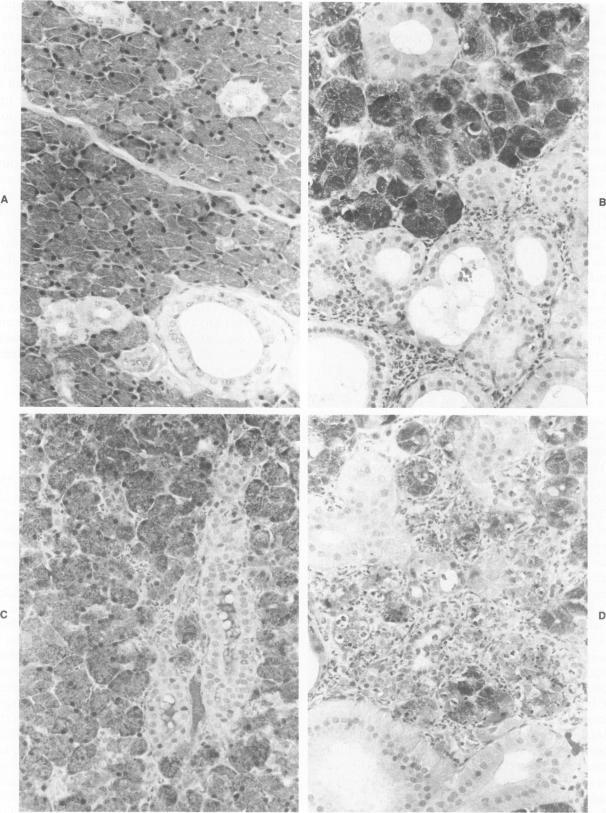

Acute and chronic salivary gland dysfunction are common sequelae of radiotherapy for head and neck cancer; but the associated morphologic changes, especially of the acute damage, have received relatively little study. For investigation of the morphologic characteristics of acute radiation injury to parotid glands, rhesus monkeys were studied 1-72 hours after parotid irradiation with single doses of 2.5-15.0 Gy. The acute damage from all doses was clearly expressed by 24 hours. Histologically, parotid glands irradiated with 2.5 or 5.0 Gy had random degeneration and necrosis of the serous acinar cells. Doses of 7.5-15.0 Gy produced widespread degeneration along with necrosis of whole acini. Serous cell damage was accompanied by neutrophilic inflammation that subsided after 24 hours to become replaced by plasma cell and lymphocytic infiltrates. Parotid glands receiving 7.5-15.0 Gy were atrophic at 16-22 weeks after irradiation and showed no recovery by 40 weeks. Although parotid acinar cells are well-differentiated nondividing cells, these observations show that they express lethal radiation injury in interphase within hours of receiving a radiation dose as low as 2.5 Gy. This is unlike most mammalian cells that express radiation injury during mitosis. Chronic atrophy is a consequence of this direct, irreversible, and early injury, rather than the result of radiation-induced changes in the vasculature.

急性和慢性唾液腺功能障碍是头颈癌放疗常见的后遗症;但相关的形态学变化,尤其是急性损伤的变化,研究相对较少。为了研究腮腺急性放射性损伤的形态学特征,对恒河猴单次腮腺照射2.5 - 15.0 Gy后1 - 72小时进行了研究。所有剂量的急性损伤在24小时时均明显表现出来。组织学上,接受2.5或5.0 Gy照射的腮腺浆液性腺泡细胞出现随机变性和坏死。7.5 - 15.0 Gy的剂量导致广泛变性以及整个腺泡坏死。浆液细胞损伤伴有中性粒细胞炎症,24小时后消退,继而被浆细胞和淋巴细胞浸润取代。接受7.5 - 15.0 Gy照射的腮腺在照射后16 - 22周出现萎缩,至40周仍未恢复。尽管腮腺腺泡细胞是分化良好的非分裂细胞,但这些观察结果表明,它们在接受低至2.5 Gy的辐射剂量后数小时内的间期就表现出致死性辐射损伤。这与大多数在有丝分裂期间表现出辐射损伤的哺乳动物细胞不同。慢性萎缩是这种直接、不可逆和早期损伤的结果,而非辐射诱导血管变化的结果。